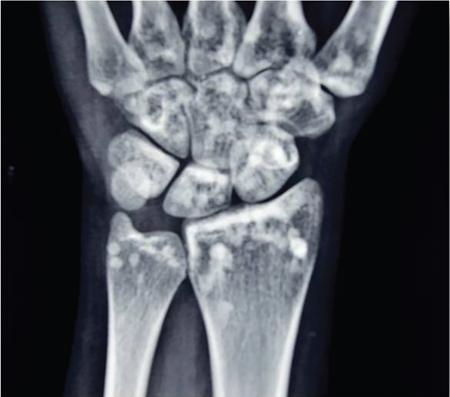

MISCELLANEOUS PAEDIATRIC RADIOGRAPHY – TECHNIQUES AND INTERPRETATION: SKELETAL SURVEY Padma V. Badhe The skeletal survey, generally performed in children, is a set of radiographs done in order to evaluate the entire skeleton. A skeletal survey, commonly used to evaluate skeletal dysplasias, acquired metabolic disorders and suspected child abuse, is still the key radiological investigation for the same. Hence, an explicit understanding of the technique along with the common disorders forms the basis of making a diagnosis in these paediatric pathologies. A skeletal survey is done for various skeletal dysplasias, non-accidental injury (battered baby syndrome) and suspected child abuse. It can also be done in cases of metabolic bone diseases, disseminated infections, multiple myeloma, eosinophilic granuloma. It is also used in evaluation of metastatic bone diseases and polyarticular arthropathy. Orthogonal views of the skull, spine, pelvis and one extremity are taken, preferable in standing position. For preterm babies/newborns, AP and lateral views of babygram may be taken. Projections: For skeletal dysplasias: Additional views: Both extremities may be taken if epiphyseal abnormalities and limb asymmetry is present. Focused views for specific pathologies may be taken. When a diagnosis remains uncertain, 1 year follow up is usually recommended. For preterm babies/newborns: AP and lateral views of babygram may be taken with additional specific views for extremities. For suspected non-accidental injury (NAI): AP and oblique view of chest is taken for better evaluation of the ribs. AP view of abdomen with pelvis. Both upper and lower limbs are evaluated. In lower limbs, two projections in AP and lateral (one with both femur including hip and knee joints; and another for foot and ankle) is taken. AP and lateral views of whole spine, skull. Oblique view of hands. A babygram should be avoided in cases of NAI, as subtle fractures are easily missed. Proper legal documentation while taking the views is very important and ideally two health care professionals must be present. For metabolic disorders: entire skeletal survey is usually not required. Specific views of hands, knees and spine may be taken with additional views depending on the suspected pathology. Centring point: Varies according to the part being examined. Angulation, collimation and orientation: Varies according to the part being examined. Images must be well collimated to obtain lower radiation dose. Detector size: Varies according to the part being examined: 8″ × 10″, 10″ × 12″, 11″ × 14″. Exposure: Ideally high kVp images are taken to reduce radiation dose. But in suspected NAI, low kVp/high mA images are recommended to better demonstrate findings. SID (Source Image Distance):100 cm Grid: Grids are not routinely used to image spine, pelvis, skull and abdomen in children. Radiation dosage: 0.3–3 mSv Essential image characteristics: Adequate spatial resolution, high signal to noise ratio, low kVp (50–70) for high contrast should be done. Excellent bone and soft tissue details are required. The presentation of skeletal dysplasia can range anywhere from minimal stunting of growth and bowing of limbs to severe dwarfism and multiple fractures. Knowledge of the commonly encountered dysplasias with an approach to arrive at a diagnosis is vital in any Radiologist’s practice The following flow chart summarizes the classification of important skeletal dysplasia: The following table summarizes the various dysplasias affecting the axial skeleton: TABLE 7.5.1.1 The following flow chart summarizes the working approach to skeletal dysplasias: Osteopetrosis (Albers-Schonberg disease/Marble bone disease) (Fig 7.5.1.1): Osteopetrosis clinically presents with anaemia/thrombocytopenia or cranial nerve compression. Radiological features include generalized increase in bone density with loss of medullary space. However, cortico-medullary appreciation with cortical thinning is also rarely seen. Bone within bone appearance with Erlenmeyer flask deformity is also noted. Pyknodysostosis (Figs. 7.5.1.2 and 7.5.1.3): patient presents with short stature. Unlike osteopetrosis, there is no anaemia. Radiographs show generalized increase in bone density with preserved medullary canal. There is mandibular hypoplasia with obtuse angle. Acro-osteolysis is also a feature. Dental caries with osteomyelitis of the jaw may be seen. Sclerosing dysplasia presenting as wavy undulating new bone formation. Usually monomelic, lower limb and along one side. The classic appearance is described as Dripping candle Wax sign. It is a Sclerosing dysplasia with radiological features of symmetric juxta-articular involvement in epimetaphyseal region. They are 1–10 mm in diameter and uniform in size. No metabolic activity is seen on bone scans. This skeletal dysplasia shows diffuse decrease in bone density with paper-thin cortex. Fractures heal in normal time but shows callus with poorly cellular matrix. Wormian bones and enlarged sinuses may be seen. Codfish vertebra (Biconcave vertebra) may be seen. Metaphyseal corner fractures are not seen in osteogenesis imperfecta that helps to differentiate it from battered baby syndrome. There are four types of OI out of which type one is most common (Figs. 7.5.1.6 and 7.5.1.7). The radiological features of MPS include Osteopenia and Universal platyspondyly. The intervertebral disc spaces are maintained. Proximal pointed metacarpals is an important radiological finding. Hurler’s syndrome show anteroinferior beaking with short and wide metacarpals. Varus deformity of humerus is characteristically seen in Hurler’s syndrome (Fig. 7.5.1.8). Mental retardation & corneal clouding is seen in Hurler’s syndrome whereas these Hunter’s disease has normal intelligence with no corneal clouding. Morquio’s syndrome shows central beaking (Fig 7.5.1.9). This skeletal dysplasia shows normal bone density with rhizomelic limb shortening and normal trunk. Narrowing of spinal canal is classically seen with decrease in the Interpedicular distance caudally. Other radiological features include trident hand (separation of middle & third fingers), Champagne glass pelvis (short, flat ilia and small sciatic notch), bullet nose vertebra and overexpansion of skull with narrow foramen magnum (Fig. 7.5.1.10). This skeletal dysplasia is characterized by normal bone density with dwarfism and normal craniofacial skeleton. The interpedicular distance is normal. There is severe platyspondyly with anterior tonguing (disappears at older age). Other radiological features include increased disc space, short stubby metacarpals, small irregular epiphysis and widened metaphysis. Anterior tonguing is a feature of Pseudoachondroplasia. This form of skeletal dysplasia involves the spine and epiphyses (Fig. 7.5.1.11). There is normal bone density with rhizomelia. Spine and Pelvis can be involved. Premature osteoarthritis can be seen. The other characteristic features include Platyspondyly and small irregular epiphysis. There are two forms Spondyloepiphyseal dysplasia Congenital and Spondyloepiphyseal dysplasia Tarda. Spondyloepiphyseal dysplasia Congenita is Autosomal dominant and shows pear-shaped vertebrae. Spondyloepiphyseal dysplasia Tarda is X Linked recessive with heaped up vertebrae. It has two forms. The first form is Conradi Hunermann syndrome which is autosomal dominant characterized by asymmetric limb shortening with metaphyseal flaring (Fig. 7.5.1.12). The Autosomal recessive form is Fatal in first few years. Rickets: Rickets refers to deficient mineralization of the growth plate in the paediatric population due to deficiency of vitamin D. In an immature skeleton, there is abnormal mineralization at the zone of provisional calcification in the metaphysis due to osteoid deposition resulting in widening of the growth plate. The features of rickets include fraying, splaying and cupping (Fig. 7.5.1.13). Fraying denotes indistinct margins of the metaphysis whereas splaying denotes widening of metaphyseal ends. Term ‘Cupping’ is used for increased concavity of the metaphysis. These findings are typically seen involving areas of active growth (e.g. distal femur and proximal tibia in the knee) Bowing is a result of associated osteomalacia leading to weakening of weight-bearing lower limb bones. Other bone deformities such as genu valga, genu varum, protrusio acetabuli can also be seen. The lower ribs may also be drawn inwards inferiorly by the attachment of the diaphragm this is called Harrison’s sulcus. Scurvy: Scurvy is a result of dietary deficiency of Vitamin C (ascorbic acid). The classic presentation is that of a patient with an increased bleeding tendency and osteopenia with poor wound healing. Features of scurvy include generalized osteopenia with cortical thinning termed as ‘pencil-point’ cortex. Other radiological findings include the periosteal reaction due to subperiosteal haemorrhage. Expansion of the costochondral junctions occurs forming scorbutic rosary. Bleeding into the joint spaces may result in hemarthrosis. Circular, opaque radiologic shadow surrounding epiphyseal centres of ossification may result from bleeding (Wimberger ring sign) (Fig. 7.5.1.14). Frankel line may be seen. It represents dense zone of provisional calcification. Lucent metaphyseal band is seen underlying Frankel line called as Trümmerfeld zone. Metaphyseal spurs may be seen that result in cupping of the metaphysis (Pelkin spur). Pelkin fracture (metaphyseal corner fracture) can also be seen. Images obtained must be of good resolution with adequate bone and soft tissue details. Additional views: They have already been described in positioning. CT Brain in can be done in cases of NAI to look for subdural hematomas. A skeletal survey is the first-line imaging modality for evaluation of skeletal dysplasia, nonaccidental injury and metabolic bone diseases. The skeletal survey must be tailored according to the respective indication. It helps to characterize syndromic patterns in skeletal dysplasias, with evaluation of complications. In cases of diagnostic dilemmas, additional focused view and occasionally yearly follow-up is recommended. A high index of suspicion is needed in utilizing skeletal survey as a diagnostic modality in NAI. At the same time, one must also remember the legal and social implications of making this diagnosis. BABYGRAM Babygram is a colloquial term used for a radiograph of the whole body of a newborn or just the chest and abdomen (thoracoabdominal babygram) on a single image. As the name suggests it is a rather non-targeted study. It is most commonly requested after line placement. Evaluation of skeletal abnormalities in a deceased foetus is typically performed using anteroposterior and lateral views of a babygram. It helps in pointing out skeletal causes of death in stillborn or dead foetuses. This will help the treating physician and parents understand the reason for baby’s death. This will also help in future genetic counselling of the couple. Sometimes chest or abdominal radiographs of the baby are requested but due to radiographers error or inexperience with small babies, there is inclusion of the region not to be assessed leading to a false babygram. Babygram is most frequently done after line placement in neonates, to view the position of the umbilical vein or artery catheter and to confirm appropriate placement. It is a useful modality in skeletal dysplasias (Fig. 7.5.1.15) like osteogenesis imperfecta, thanatophoric dysplasia and chondrodysplasia punctata. It can also be used for skeletal deformations probably caused by foetus akinesia and in cases of Caudal regression syndrome. In stillborn foetuses, it is used for evaluation of skeletal dysplasias prior to an autopsy (Fig. 7.5.1.16). It is also used in screening for surfactant deficiency and in cases of Necrotizing Enterocolitis in preterm babies where it can help to see the bowel dilatation, intramural and portal venous gas. It can be done in aneuploidies like trisomy 18 and in cases of sudden infantile death syndrome. All the essential equipment and room need to be prepared including the exposure factor. This should be done prior to placing the baby on the table to prevent any neonatal heat loss. Ensure that the baby is correctly identified. Give brief explanation to the patient’s parents regarding the procedure, its risks and benefits. Ensure that the accompanying relative is not pregnant (if female). Parents/guardians/nurses should be instructed to hold the baby with arms above the head and legs straight down. Sandbags/tapes can be used to immobilize the baby. Avoid taking the radiograph when baby is crying. Normal appearance: The endotracheal tube should lie in the lower third of trachea, distance can vary with position of baby’s head. Umbilical artery catheter has an inferior dip along the internal iliac artery, which then turns superiorly along the aorta. The tip should lie in the mid-thoracic aorta (T6–T10) or lower (L3–L4) away from aortic branches to prevent any thrombosis. Umbilical venous catheter does not have the inferior curvature, but rather a posterolateral angulation to the right near the liver through the ductus venosus. The tip should lie in the superior IVC or right atrium at T8/T9 vertebral level (Fig. 7.5.1.17). Portal venous gas may be seen initially after insertion. In a stillborn foetus, the approximate gestation age of the foetus and corresponding ossification centres must be known. In early gestation, the lack of appearance of an ossification centre may be mistaken for skeletal dysplasia. Both chest and abdomen should be included. In a rotated patient, the distance between the spinous process to medial end of clavicles will be asymmetric. The medial end of clavicle should overlap the lung apex, if above, suggests lordotic image. Motion artefacts to be reduced as much as possible. A crying neonate may result in an expiratory film, and hence must be evaluated accordingly. In evaluation of skeletal dysplasias in the newborn, additional views of skull and hand have to be obtained. Baby gram is a useful diagnostic investigation for position of the paediatric umbilical catheters. It helps in general survey in skeletal dysplasia (Fig. 7.5.1.18). It is a simple, effective study in deceased foetus for diagnosis and further counselling, sometimes obviating the need for an autopsy. As baby gram is a non-targeted study, it increases the dose of radiation for the baby. As the exposure settings remain same for the entire body of the baby, the quality of the image decreases. This increases the chances of missing subtle findings. The babygram in a neonate is currently used to localize umbilical catheters. In stillborn fetuses, it is still an important study for documenting and confirming skeletal dysplasias. Understanding the normal appearance as per gestation age and patterns of various common skeletal dysplasias is essential for evaluation. Being a non-targeted study, it should not be used as an alternative study to evaluate the chest or abdomen considering radiation exposure and poorer image quality. INVERTOGRAM Invertogram was first described by Wangensteen and Rice in 1930. It was used as a first investigation to be ordered in evaluation of infants with clinically diagnosed or suspected Anorectal Malformation (ARM). ARM is a serious but surgically treatable congenital malformation with approximate incidence of 1 in 5000 live births. Though the diagnosis of this condition is based on clinical history and physical examination, imaging plays an important role in deciding the type of ARM, and associated complications to aid in management. International classification of anorectal malformations is as follows. Syndromic association is seen as a part of VACTERL defects, trisomy 21 13 and 18, Klippel Feil syndrome, cat eye syndrome etc. The main indication of Invertogram is to evaluate anorectal malformation in a neonate. A radio-opaque marker is placed over the external anal opening. Infant is held inverted by holding both thighs, maintaining this posture for at least 5 minutes before taking an X-ray in true lateral position (Fig. 7.5.1.19). Exposure is made during inspiration. The Invertogram should ideally be done 24 hours after birth as, the rectal gas may not reach the terminal segment if study is done too early. Pubo-coccygeal line (PCL) is drawn from upper border of pubic symphysis (which corresponds to centre of pubic bone on lateral X-ray) to sacrococcygeal junction. I point is the inferior most point of ischial ossification centre. A line which is drawn parallel to PC line passing through the I point is called I line. ‘A’ point is represented by marker placed at anal pit. The position of rectal pouch gas shadow is observed with respect to these lines and appropriate diagnosis is made (Fig. 7.5.1.21). A diagnosis of high ARM is made when gas shadow of rectal pouch is cranial to PCL. If rectal pouch gas shadow is in between PCL and I line, it is called as intermediate ARM and if it is caudal to I line, it is diagnosed as low ARM. Gas in urinary bladder or vagina or beaking of gas shadow of rectal pouch indicates fistula into one of these sites. Associated congenital abnormalities like spinal defects are also looked for in the invertogram (Fig. 7.5.1.22). Invertogram done too early (less than 24 hours) may not demonstrate rectal gas. Meconium plugging the terminal segment gives false position of the rectal gas. Positioning can cause discomfort to child and an irritated crying child actively contracts the sphincter muscles, pushing the gas shadow higher. Rectum may be pulled cephalad due to gravity in inverted position. The rectal gas may escape through an associated fistula. Erroneous interpretation can also occur due to sacral anomalies and when gas in vaginal cavity is misinterpreted as distal rectal gas. Both ischial bones should superimpose and terminal blind loop should be well distended. It is an easily available modality and can be done quickly, does not require additional equipment. It has lesser radiation dose as compared to CT invertogram. It provides a rough guide as to the type of ARM and decides management. Higher localization of obstruction due to various causes like meconium plugging, imaging done too early etc. as described above in pitfalls. It is more uncomfortable to the baby as compared to the prone cross-table lateral view, and a crying baby contracts the puborectalis leading to erroneous results. K. L. Narasimharao et al. modified the technique and proposed cross-table lateral view for evaluation of infants with ARM’s which has shown equal or better information and has now replaced invertogram (Fig. 7.5.1.23). Prone cross-table lateral view is considered equivalent or even better in determining the level of anomaly. Positioning is in this view is prone in genupectoral position (at least for 3 minutes). It is taken in true lateral and during inspiration. The lines used to delineate types of ARM is essentially the same as in an invertogram. It is preferred over invertogram as relatively easy positioning of the infant and less discomfort allows for better cooperation of neonate during the study. It also eliminates the effect of gravity. ARM with fistula is better delineated as, in an invertogram, fistula/gas is at the highest level and gas may escape through it. CT invertogram is another modality that delineates anatomy better but is rarely used. In the era of cross-section imaging, MRI and USG have opened new modalities for accurate diagnosis of ARM, but invertogram being readily available, inexpensive, quick and cost-effective is used as first investigation for evaluating a patient with suspected or confirmed case of ARM. Cross-table lateral view has replaced invertograms as it is more patient-friendly and equally effective. UPPER GASTROINTESTINAL SERIES Rushit S. Shah An upper gastrointestinal (GI) study is a radiographic examination of the GI tract from the pharynx to the ligament of Treitz after oral administration of contrast agent. The use of upper GI studies is gradually declining with the increasing availability of paediatric endoscopy and the challenge for the modern radiologist to work in conjunction with the surgeon and gastroenterologist to select the right patients for an upper GI series. However, the upper GI series remains the key for demonstrating many anatomical abnormalities. The upper GI series is also useful in evaluating gastro-oesophageal reflux in conjunction with 24 pH monitoring. The upper GI examination is useful in evaluating many conditions including but not limited to: